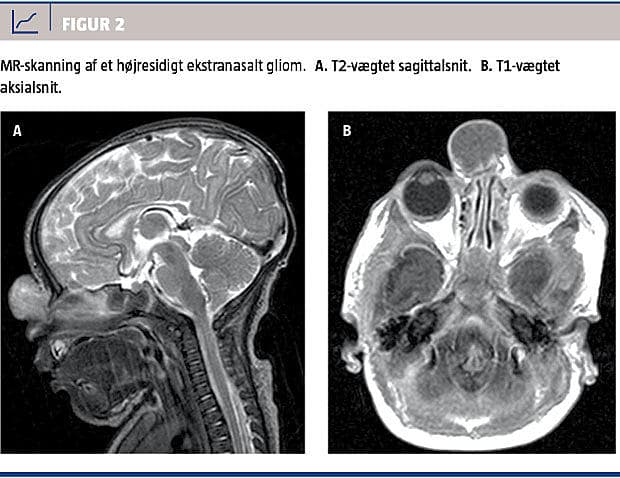

De to mest anvendte billeddiagnostiske undersøgelser i diagnosticeringen og den kirurgiske planlægning af KNMT er CT og MR-skanning. Konventionelle røntgenbilleder og knogletomografier er i dag obsolete. Det er af afgørende betydning for den videre behandling at be- eller afkræfte en intrakranial forbindelse, da en evt. kraniotomi afhænger af dette. CT giver de bedste billeder til vurdering af knogledefekter i lamina cribrosa og os frontale, hvilket kan tyde på en intrakranial forbindelse, men desværre er en knogledefekt langtfra ensbetydende med, at der er en sådan, og fundet er i forskellige studier falsk positivt hos helt op til 37% [12, 18]. MR-skanning er bedst, når man ønsker at fremstille bløddele, og giver med kontrast differentieret information om typen af det væv, tumoren består af. Dette kan allerede præoperativt give et fingerpeg om den sandsynlige diagnose. Herudover vil en persisterende intrakranial forbindelse erkendes i de fleste tilfælde. Kombineret med den manglende ioniserende stråling gør det MR-skanning til den foretrukne undersøgelse til diagnostik og præoperativ vurdering af KNMT [7, 18] (Figur 2). MR-skanning af små børn kræver generel anæstesi, og hos børn under to år er det forbundet med en øget risiko. Derfor kan man afvente skanning til efter barnets andet leveår, såfremt man kan udelukke malignitet eller encefalocele. Er tumoren sikkert til stede fra fødslen, kan malignitet udelukkes, og er den lokaliseret distalt for ossa nasales, er det ikke et encefalocele. Ved proksimal lokalisation eller tvivl bør barnet skannes tidligere (Figur 3).